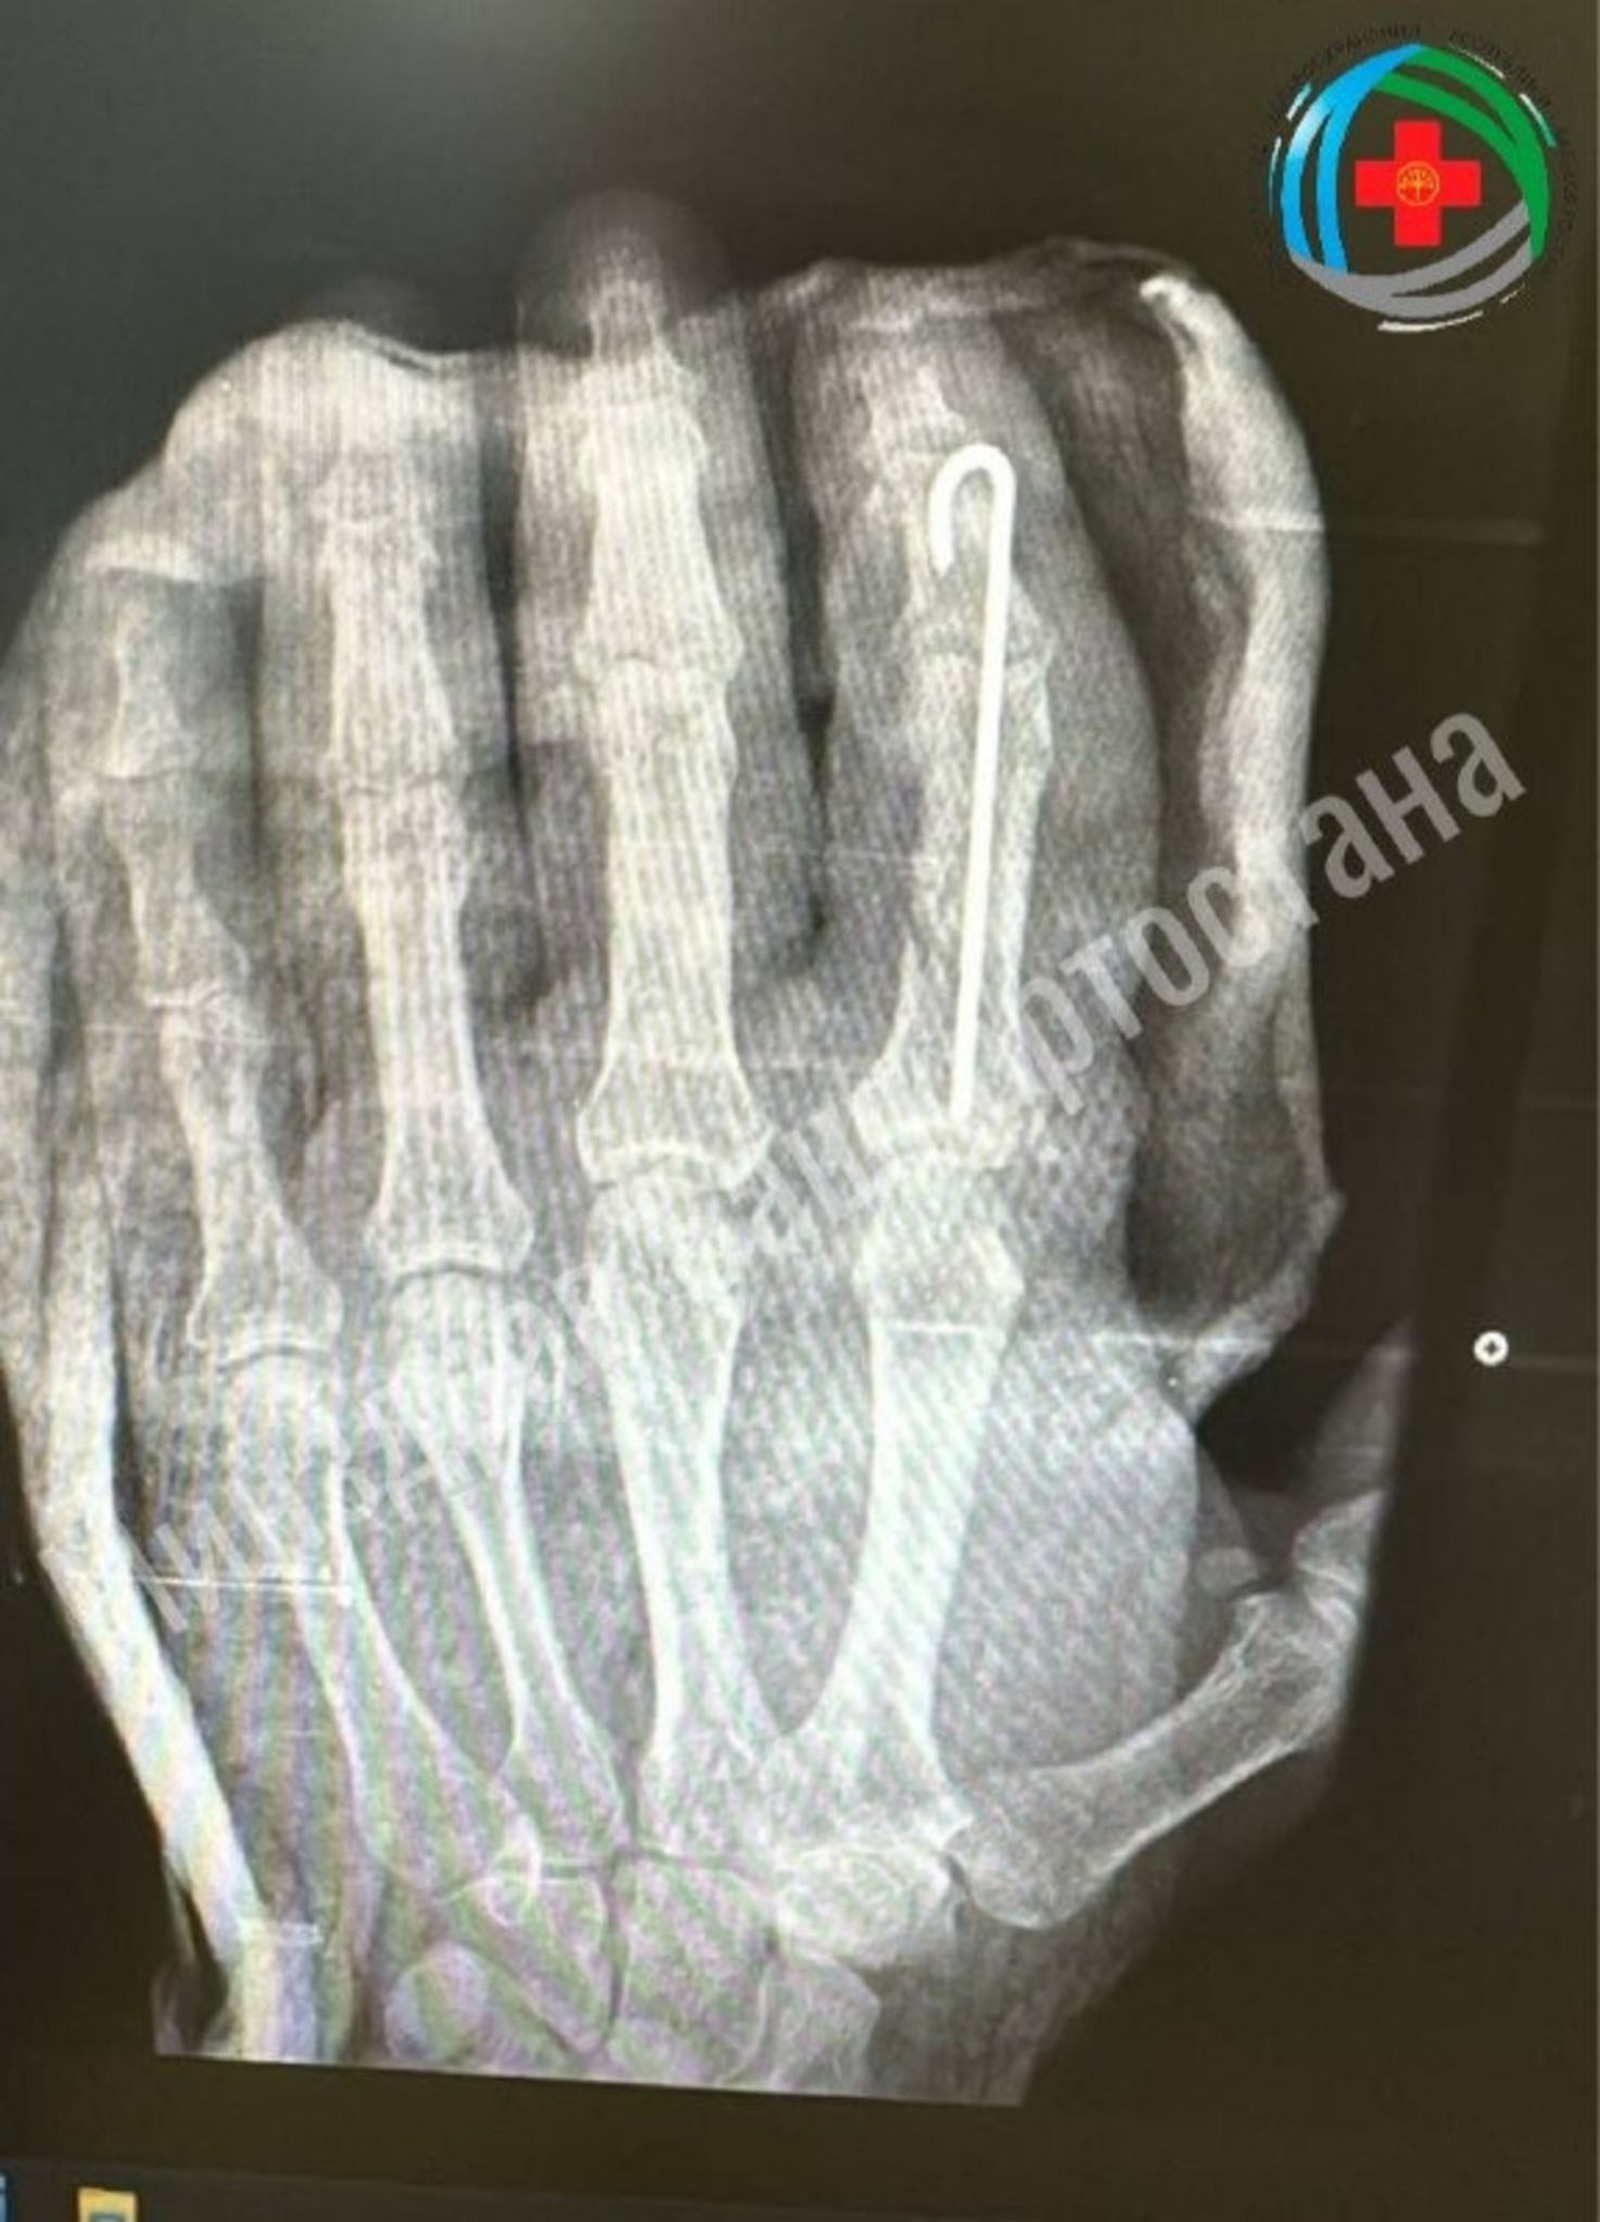

Жителю Благовещенского района врачи местной больницы успешно пришили ампутированный палец.

Мужчина случайно отрубил себе палец руки топором. После осмотра хирурги приняли решение о проведении экстренной операции.

Они провели по-настоящему ювелирную работу: восстановили мельчайшие сосуды для возобновления кровотока, точно зафиксировали кости и реконструировали мягкие ткани, чтобы сохранить полноценное движение пальца, сообщает "Башинформ".

Орган прижился удачно, мужчина уже может немного пошевелить им. Сейчас он проходит восстановительное лечение, которое включает медикаментозную терапию, физиотерапию и лечебную физкультуру. По результатам лечения ожидается полное восстановление функций пальца.

Фото: минздрав РБ / пресс-служба